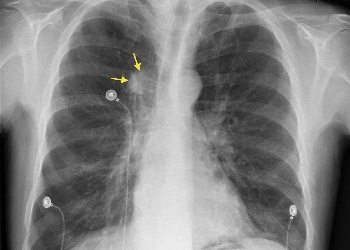

奥希替尼是第三代EGFR酪氨酸激酶抑制剂,主要用于EGFR突变阳性的肺癌(NSCLC),其适应症涵盖一线治疗(如初治EGFR敏感突变晚期患者、局部晚期不可切除Ⅲ期患者)、二线治疗(T790M突变耐药患者)及术后辅助治疗(IB-IIIA期术后患者);优势在于精准抑制EGFR敏感突变及T790M耐药突变,显著延长患者无进展生存期(中位PFS达18.9-29.4个月)和总生存期(中位OS超38.6个月),且可穿透脑屏障有效控制脑转移,降低疾病进展或风险。

甲磺酸奥希替尼片(Osimertinib、奥希替尼、泰瑞沙、AZD9291),作为全球首个第三代EGFR-TKI抑制剂,自2017年3月在国内上市以来,已成为治疗局部晚期或转移性非小细胞肺癌(NSCLC)的重要方案。特别是对于存在表皮生长因子受体(EGFR)外显子19缺失或外显子21(L858R)置换突变的NSCLC患者,奥希替尼被视为一线治疗方案。奥希替尼因为远超同类的疗效,成为EGFR突变非小细胞肺癌当之无愧的首选“神药”!刚上市时,奥希替尼价格高达5万多,经过几轮的医保降价后,奥希替尼便宜很多,奥希替尼医保价格:奥希替尼的药房零售价格,各地存在差异。在国内,国产奥希替尼还未上市,进口奥希替尼医保报销后价格大约为5300元(80mg*30片),长期使用下来,负担比较重,很多患者把目光转向印度奥希替尼,因为印度奥希替尼价格便宜,并且印度奥希替尼效果和英国原厂进口保持一致,如今印度奥希替尼多少钱一瓶,印度奥希替尼多少钱一盒?印度奥希替尼一盒价格大约在每盒2880至3000元之间,一盒规格为80mg/粒,30片装。印度奥希替尼代购,印度奥希替尼哪里买?